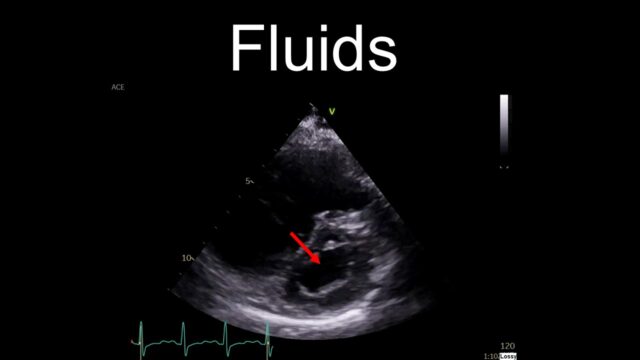

How do we support the circulation?

Our default reaction, understandably is to reach for fluids. It is almost always a reasonable thing to do but I’m going to suggest we don’t do that here. If someone is hypotensive in the context of PE then their RV is failing. It is blown out and flaggy. The septum will be squeezed over and impairing LV filling. Dumping a litre of crystalloid into the venous circulation is going to do nothing but make this worse, raising the CVP and pushing the septum further over. This is why I have put fluids in the “not helpful” category